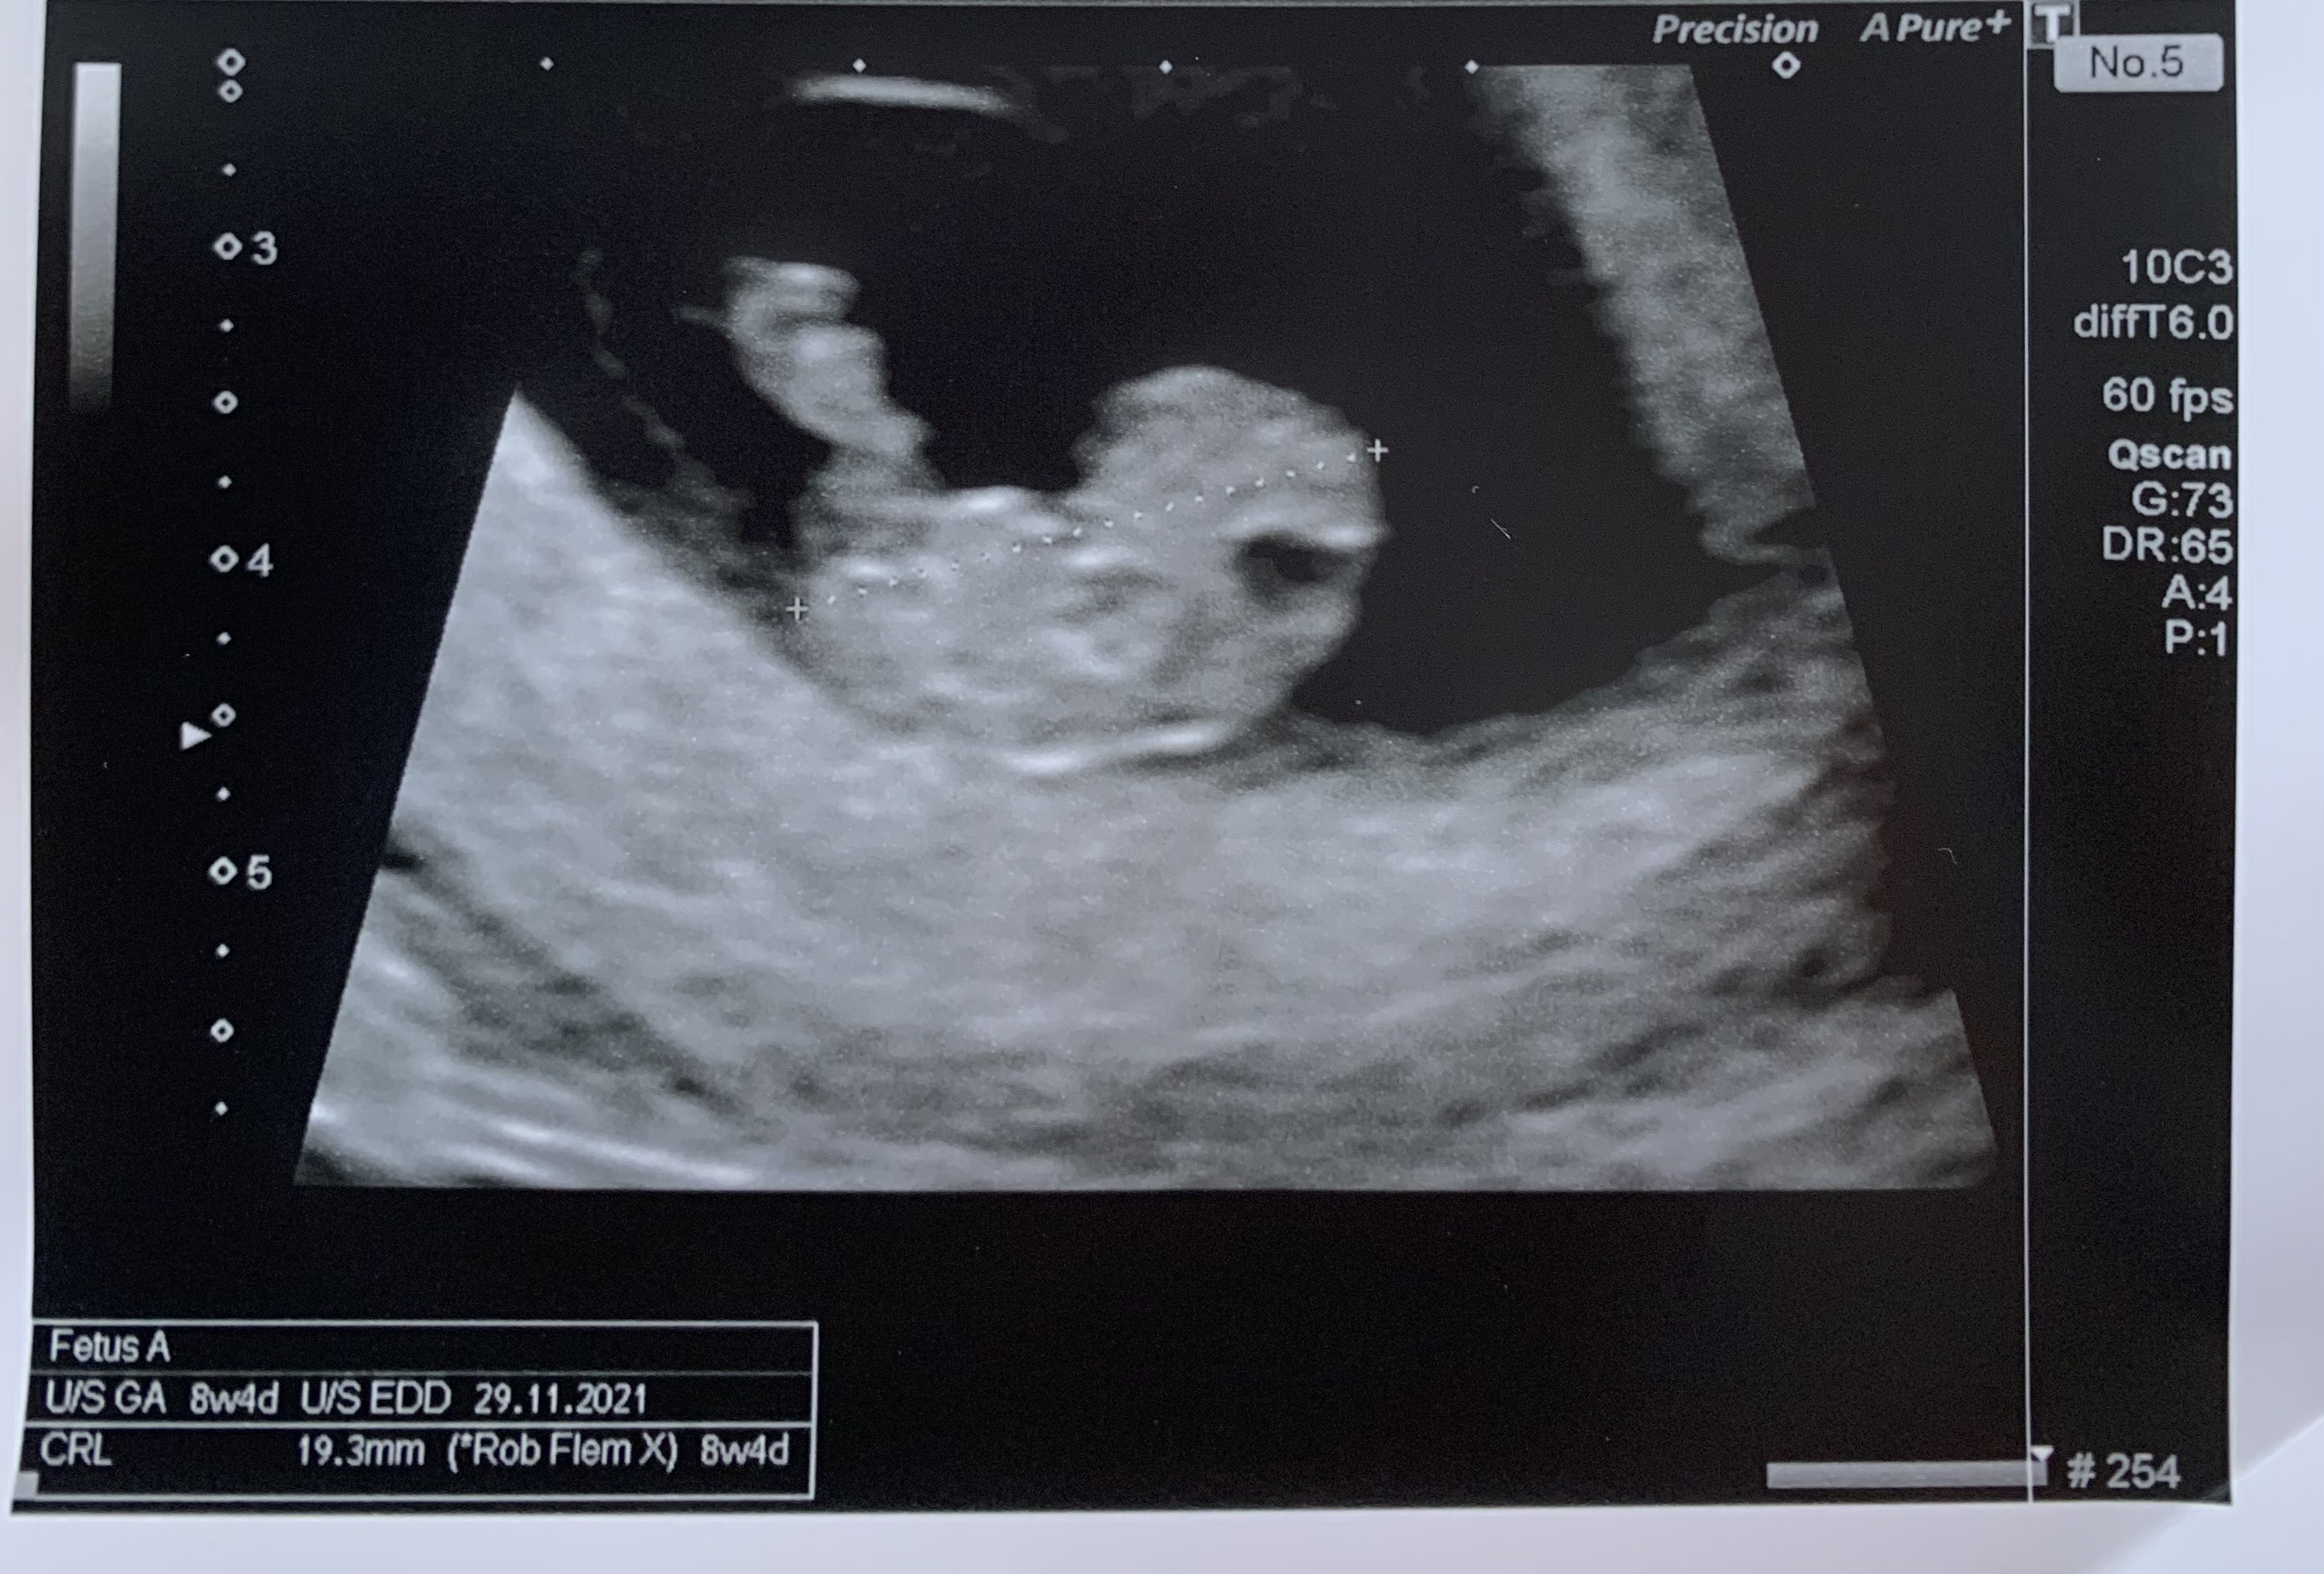

jeju, już tak dużo widać! Jak będę 6.05 na kolejnej wizycie to będę 9+1 dzień. Nie mogę się doczekać. Piękny dzidziuś ❤️

Popłakałam się na tym usg , bo w poniedziałek miałam lekkie plamienie i byłam pewna, ze to kolejne poronienie będzie - na szczescie jest wsxystko ok 🙂